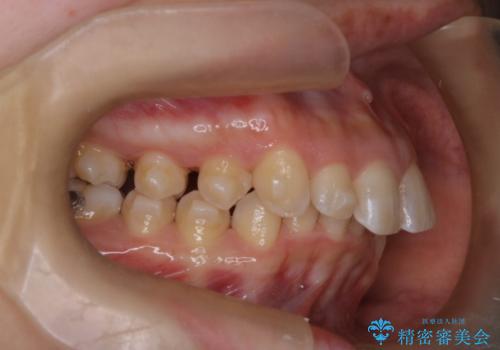

- 上の前歯の出っ歯と前歯の深い咬み合わせを治したいとのことで来院された患者様です。

上顎の歯は後方移動とIPR(歯と歯の間を削る)によって口元が引っ込むように、下顎は歯列全体の拡大とIPRによって上顎とバランスよく咬み合うように設計し、インビザラインにより治療を行うこととしました。

上顎歯列の後方への移動量が多く、右側の奥歯の咬み合わせを改善する必要もあったため、治療には長期間を要しました。